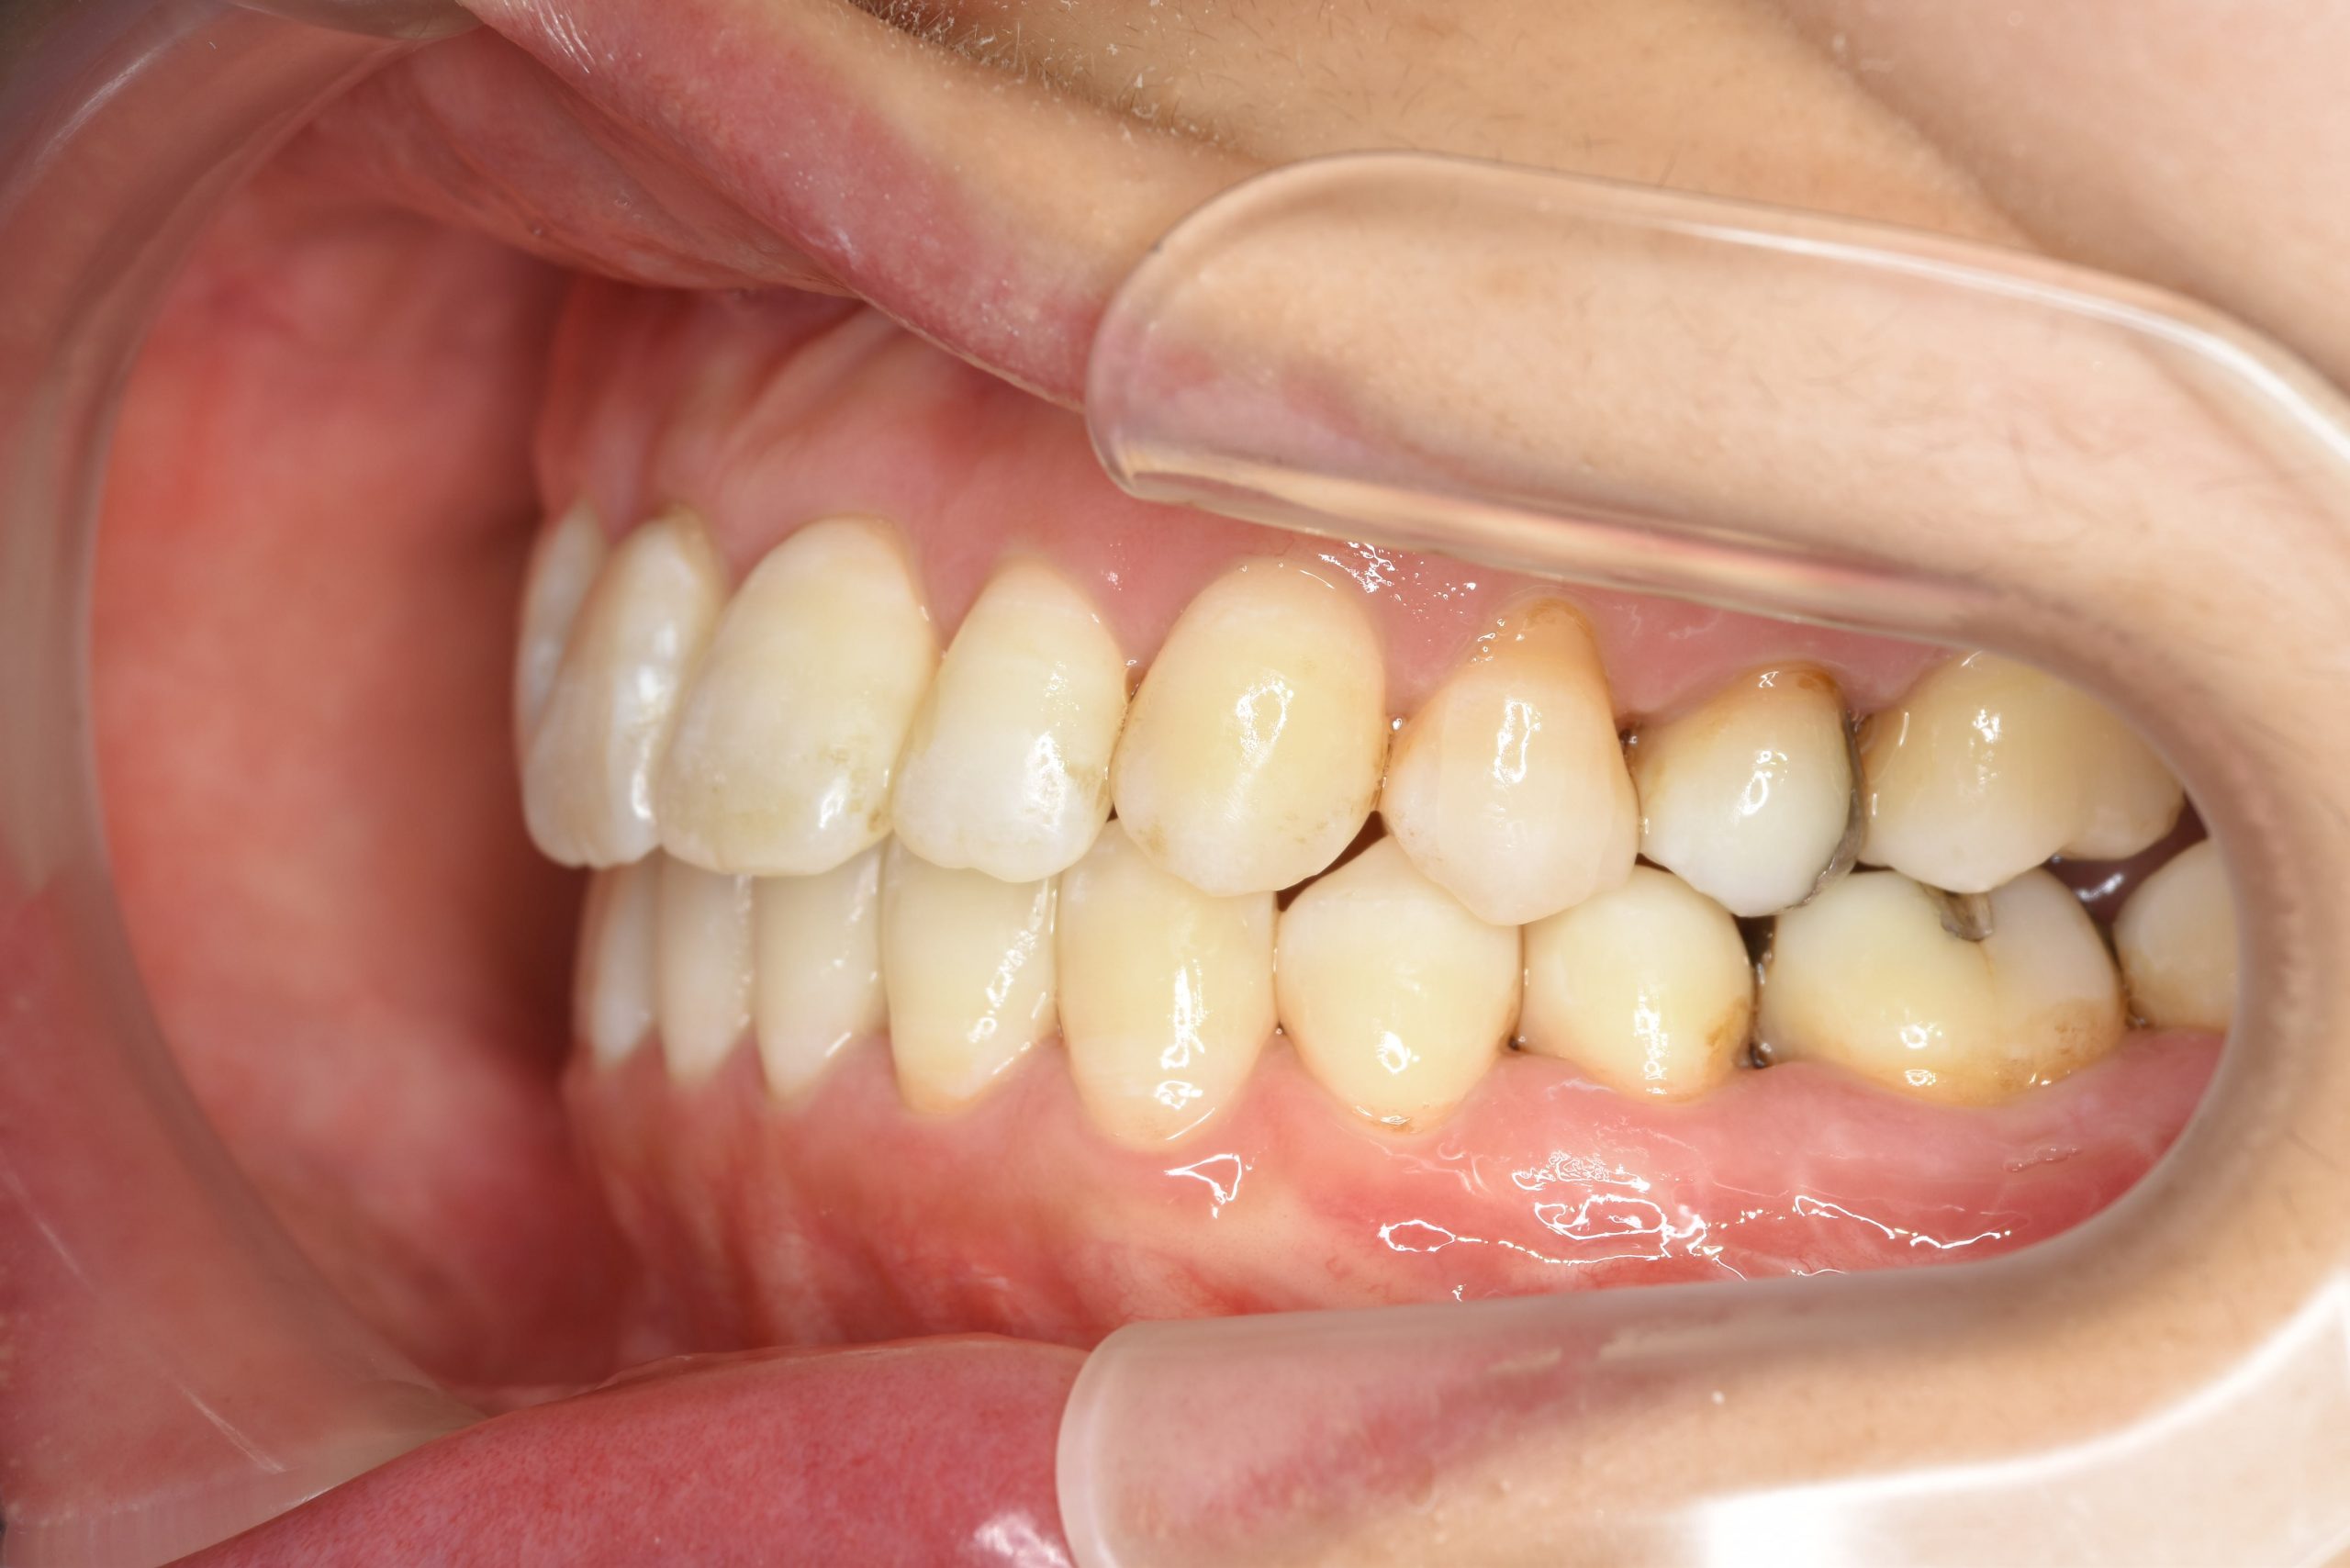

主訴 噛み合わせが悪い(反対)|歯並びが悪い|顎が出ている

施術内容 マルチブラケット装置を用いて歯牙を配列した後、

下顎骨離断術を行った。良好な咬合を獲得した。

治癒期間 3年8ヶ月間

費用 保険治療

リスク・副作用 違和感、不快感、痛み